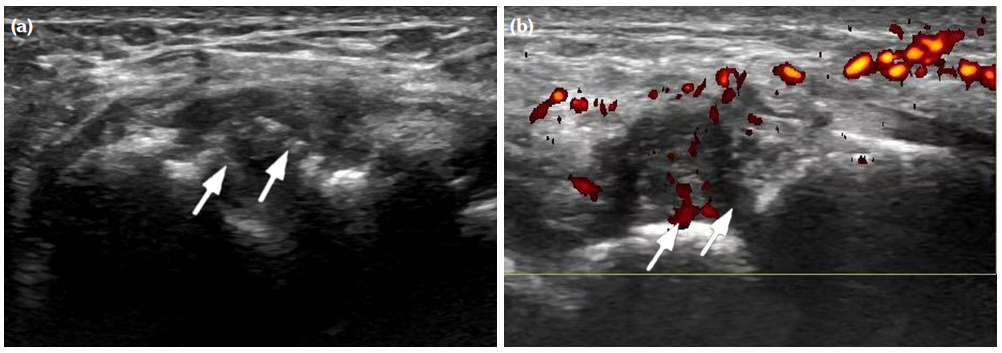

The degree of BE and synovial hyperplasia in SNRA or SPRA is more serious, and the blood flow signal is more abundant. However, the degree of synovial hyperplasia in osteoarthritis was mild, and no obvious blood flow signal was detected (Figures 1, 2, 3 and 4). Magnetic resonance imaging (MRI) studies of SPRA also showed serious BE (Figure 5).

Among SNRA, SPRA and non-RA, there was no significant difference in the grades of SH, PD, BE, nor the number of cases of tendinitis and tenosynovitis between the SNRA group and the SPRA group (p>0.05) (Table 3). There were, however, statistically significant differences in the number of cases of SH1, SH3, PD and BE grades between the SNRA and non-RA groups (p<0.001). There was no significant difference in the number of cases of SH2, PD2, tendinitis or tenosynovitis between the SNRA and non-RA groups (p>0.05) (Table 4).